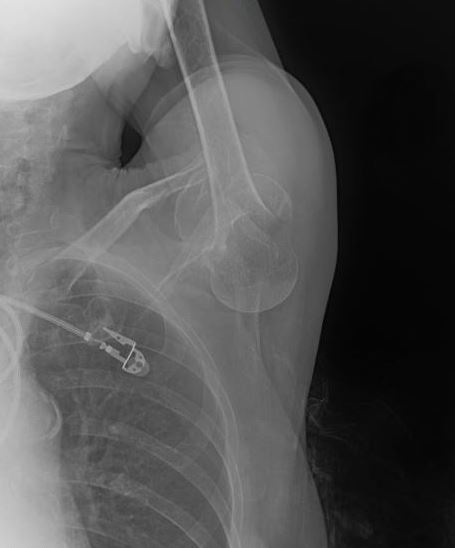

A 76 yo F presents to the ED w/ L shoulder pain. While walking her dog, the dog pulled hard on the leash and she fell, developing sudden onset L shoulder pain. On exam, her L arm is positioned above her head and she is unable to range it. X-ray is shown below. What's the diagnosis? (scroll down for answer)

Answer: Inferior Shoulder Dislocation or "Luxatio Erecta"

- Classically, patients cannot adduct their arm